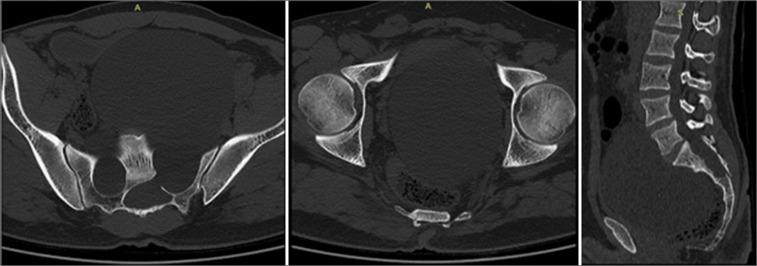

A 30-year-old male presented with a very large magnetic resonance-documented Tarlov cyst (Nabors Type 2) arising from bilateral S2 nerve root sheaths with marked pelvic extension. Although he was initially treated with a S1, S2 laminectomy, closure of the dural defect, and excision/marsupialization of the cyst, he later required placement of a thecoperitoneal shunt (TP shunt).

一名30岁男性,磁共振成像证实存在一个非常大的塔尔洛夫囊肿(纳伯斯2型),起源于双侧S2神经根鞘,并有明显的盆腔延伸。尽管他最初接受了S1、S2椎板切除术、硬脑膜缺损闭合以及囊肿切除/袋形缝合术,但后来仍需要放置脑脊膜腹膜分流管(TP分流管)。